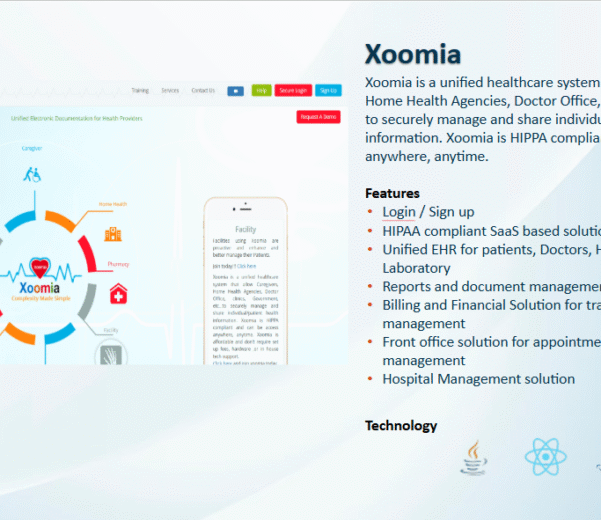

READ MORECase Study: Xoomia – Unified

Case Study: Xoomia – Unified EHR Platform for Connected Healthcare Ecosystems Problem Metric → Xoomia,...

READ MORECase Study: Xoomia – Unified

Case Study: Xoomia – Unified EHR Platform for Connected Healthcare Ecosystems Problem Metric → Xoomia,...